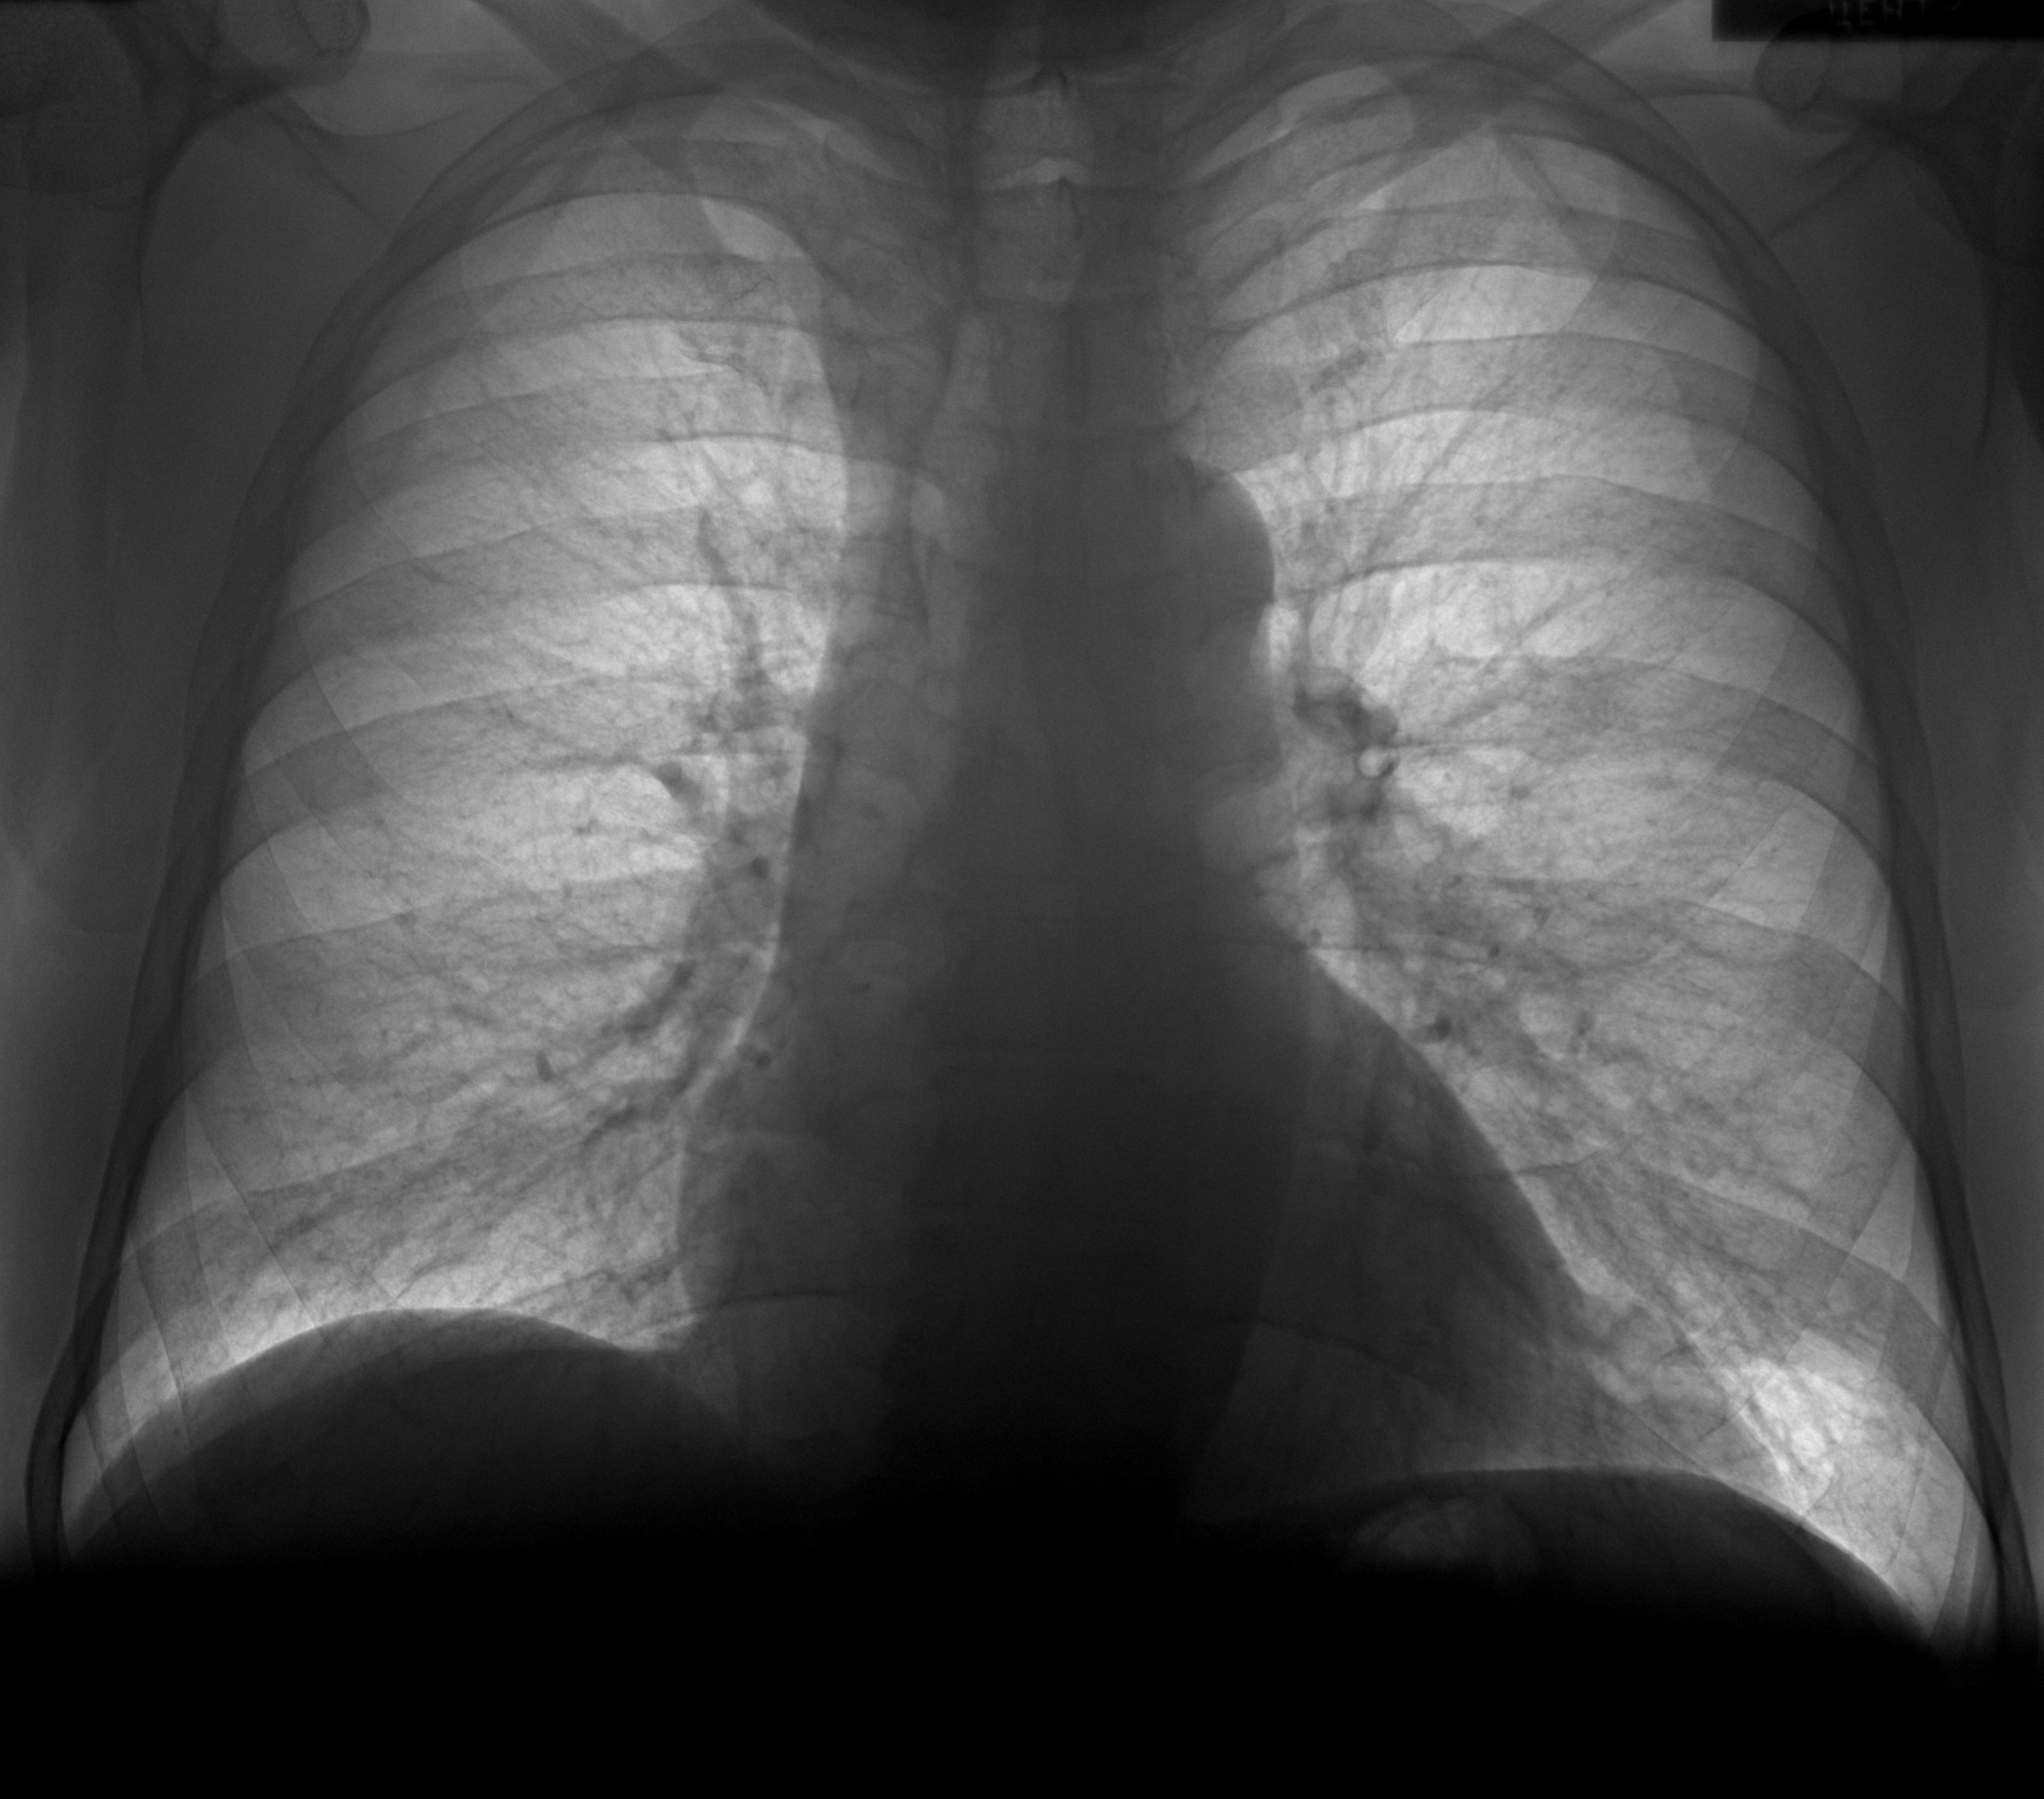

11052020 Пневмосклероз после пневмонии